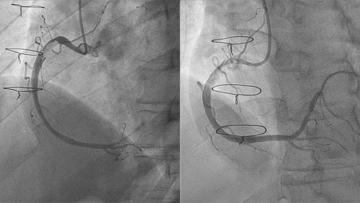

How should I treat residual large right coronary thrombus in a recent-healed #COVID19 patient with #STEMI? View part 1 of this case submitted by a team from 🇮🇹 and share how you would treat! ow.ly/3REk30rFd6w #Cardiotwitter #CardioEd

How should I treat residual large right coronary thrombus in a recent-healed #COVID19 patient with #STEMI?

View part 1 of this case submitted by a team from 🇮🇹 and share how you would treat!

How should I treat residual large right coronary thrombus in a recent-healed #COVID19 patient with #STEMI? View the treatment options retained by the authors as well as the opinion of a different team 😷🩺! pierredeharo Spychaj Jean-Charles Edgar Illescas ow.ly/bwxy30rG3ss

View the treatment options retained by the authors as well as the opinion of a different team 😷🩺! <a href="/deharo_pierre/">pierredeharo</a> <a href="/SpychajC/">Spychaj Jean-Charles</a>  <a href="/IllescasEdgar/">Edgar Illescas</a>

1/ For the fellows and #ACCEarlyCareer! It’s a coronary thrombus! When to consider thrombectomy? What do you do? Let’s walk through this…#Tweetorial #Cardiotwitter #Cardiology #STEMI

1/ For the fellows and #ACCEarlyCareer!

It’s a coronary thrombus! When to consider thrombectomy? What do you do? Let’s walk through this…#Tweetorial

“Thrombus aspiration in coronaries is a class III indication”, a statement often heard in many cath-lab. ROUTINE thrombus aspiration is a class III. It’s mandatory to make decisions case by case. #cathlab #STEMI #thrombusaspiration Giuliano.Iac Dario Prozzo